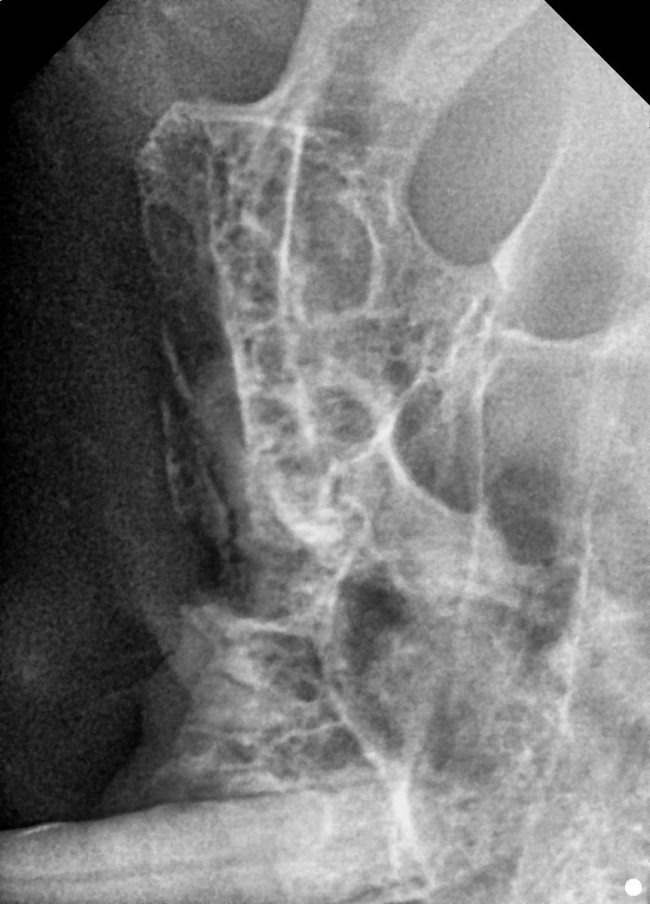

치료전 대상묘

치료중 대상묘